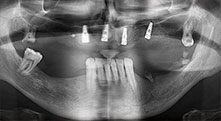

Бихте ли описали накратко, например, Вашия метод за мобилизиране на костни блокове за трансплантация?

Брату: Ние предпочитаме да събираме кост от външната страна на гребена в задната част на долната челюст. След разрязване на меките тъкани, ние използваме новите триони, за да определим количеството кост, което ще събираме. С този подход, ние използваме трионите за цялата препарация в почти 80% от случаите. Може да използваме и други пиезо инструменти и накрая длето за мобилизиране на блока. Ние смятаме, че това е изключително ефективна хирургична техника.

Брату: Ние предпочитаме да използваме техниката "сандвич" за аугментация в страничната долна челюст. Покритие на костта се подготвя с пиезо трион и кресталният фрагмент се фиксира с микровинтове. Поставяме смес от автогенна костна присадка и ксеногенен костозаместител между тях. Това работи много надеждно. Трябва винаги да осигурявате достатъчно оразмерени вертикални срезове при шиниране на алвеоларния гребен в долната челюст. В противен случай, костта лесно може да бъде счупена.